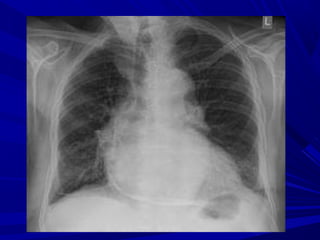

Radiological FindingsRadiological Findings

Normal <200mlNormal <200ml

Cardiomegaly >200mlCardiomegaly >200ml

+/- pleural fluid+/- pleural fluid

+/- pulmonary / mediastinal+/- pulmonary / mediastinal

- occasionally – small pulmonary infiltration or pleural- occasionally – small pulmonary infiltration or pleural

effusion (viral infection)effusion (viral infection)

- bacterial – in conjunction with pneumonia- bacterial – in conjunction with pneumonia

Chest X-RayChest X-Ray

Normal heartNormal heart

SVC distensionSVC distension

Pericardial calcificationsPericardial calcifications